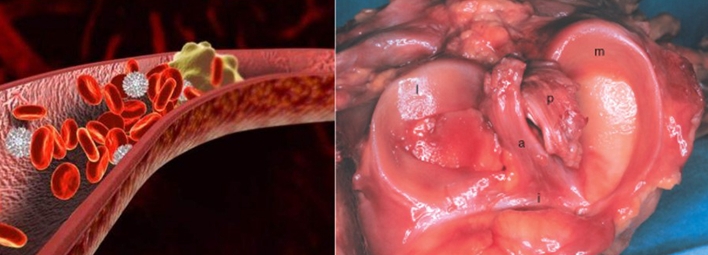

②血管源性理论:

各种原因导致微循环的继发性血栓形成,导致血管闭塞引起骨髓水肿,致使骨内压力增高和骨缺血,继而出现骨坏死。

一项研究表明,52%(13/25)患者中血栓形成相关因子水平异常,其中以高纤维蛋白原最为突出)。

另一项结果中,32例患者的因子ⅤLeiden和凝血酶原20210A基因发生率更高。这两种基因突变会引起凝血功能异常而更容易形成血栓,造成膝关节软骨下骨循环障碍而出现坏死。

2014年的一项研究中,在6名Ⅱ期SONK患者均患有血栓形成倾向,其中4名同时患有低纤维蛋白溶解,接受依诺肝素治疗的易血栓性低纤溶性患者没有出现塌陷或进展为严重的骨关节炎,并且大多数患者的疼痛得到缓解并恢复了全部功能。